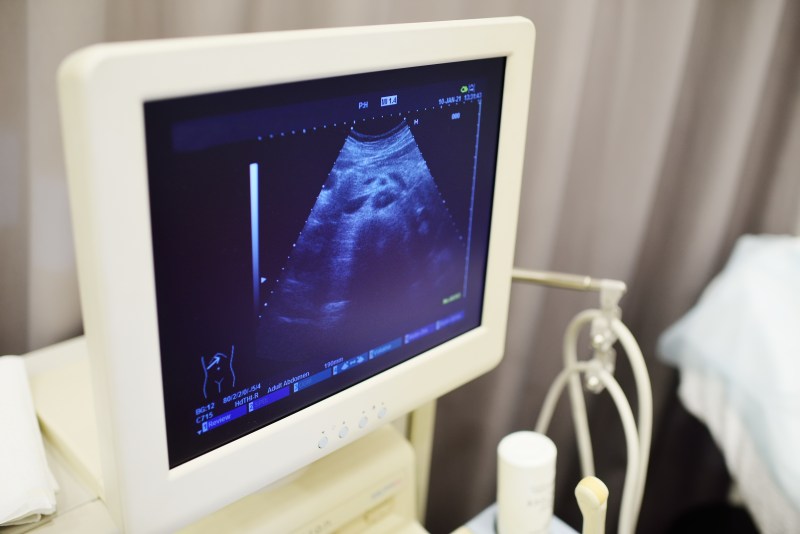

Gdy mowa o ciąży, każda przyszła mama pragnie, by jej dziecko rozwijało się zdrowo i bezpiecznie, a ultrasonografia staje się nieodzownym narzędziem, które nie tylko umożliwia monitorowanie rozwoju maluszka w łonie matki, ale także daje poczucie spokoju i pewności. To technika, która niczym magiczne okno na świat wewnętrzny organizmu, pozwala zajrzeć tam, gdzie zwykły wzrok nie sięga. Można by powiedzieć, że to taka współczesna kula czarodziejska, pokazująca niejasne jeszcze aspekty przyszłości. Bez wątpienia, ultrasonografia jest kluczowym elementem, który umożliwia monitoring zdrowia i rozwoju płodu, umożliwiając lekarzom i rodzicom podejmowanie świadomych decyzji w oparciu o dokładne dane.

Bez wątpienia, ultrasonografia jest narzędziem rewolucyjnym, które otwiera przed nami zupełnie nowe horyzonty w zakresie obserwacji i monitorowania ciąży. Wprowadzenie tej technologii do medycyny przyniosło ze sobą mnóstwo korzyści, a lekarze używają jej nie tylko do potwierdzenia obecności ciąży, ale także do oceny wieku płodu, jego rozwoju oraz wykrywania ewentualnych nieprawidłowości. Ważne jest, aby pamiętać, że ultrasonografia to nie tylko sposób na podglądanie dziecka w brzuchu – to przede wszystkim narzędzie, które w rękach specjalistów pozwala na szybkie i dokładne diagnozowanie oraz podejmowanie odpowiednich działań w przypadku zaobserwowania jakichkolwiek nieprawidłowości. Właśnie dlatego badanie to, mimo że wzbudza pewne obawy, jest zalecane przez lekarzy i uznawane za bezpieczne, o ile wykonywane jest z umiarem i zgodnie z zaleceniami.

Dla wielu przyszłych rodziców pierwsza wizualizacja maleństwa w formie obrazu z ultrasonografu to moment niemal magiczny, pełen wzruszeń i nieocenionego szczęścia. Niewątpliwie jest to jedno z tych doświadczeń, które na zawsze pozostaje w pamięci, łącząc w sobie naukową precyzję i osobiste doświadczenie. Nie bez powodu mówi się, że pierwszy obraz z ultrasonografu jest często pierwszym rodzinnym zdjęciem i symbolem zaczynającej się wielkiej przygody. Oczywiście, jak każda forma diagnozowania, ultrasonografia ma swoje ograniczenia i nie zawsze wszystko widać jak na dłoni, niemniej jednak dostarcza ona tak wielu informacji, że trudno przecenić jej rolę we współczesnej medycynie.

Podsumowując, ultrasonografia, jak żadne inne narzędzie diagnostyczne, łączy w sobie elementy współczesnej nauki i technologii z emocjonalnym aspektem oczekiwania na nowego członka rodziny. To technika, której historia sięga połowy XX wieku i która przez dziesięciolecia była doskonalona i testowana, aby ostatecznie stać się integralnym elementem opieki prenatalnej. Jej bezpieczeństwo, potwierdzone przez liczne badania i testy, pozwala przyszłym rodzicom na spokojne korzystanie z jej możliwości i cieszenie się każdą chwilą spędzoną na badaniu ultrasonograficznym. Może zmieniać i kształtować nasze zrozumienie życia jako takiego, ale jedno jest pewne: otwiera niezwykłe możliwości, które jeszcze do niedawna były jedynie domeną wyobraźni, i pozwala nam zajrzeć tam, gdzie wzrok nie sięga, odkrywając piękno i tajemnice nowego życia rozwijającego się w łonie matki.